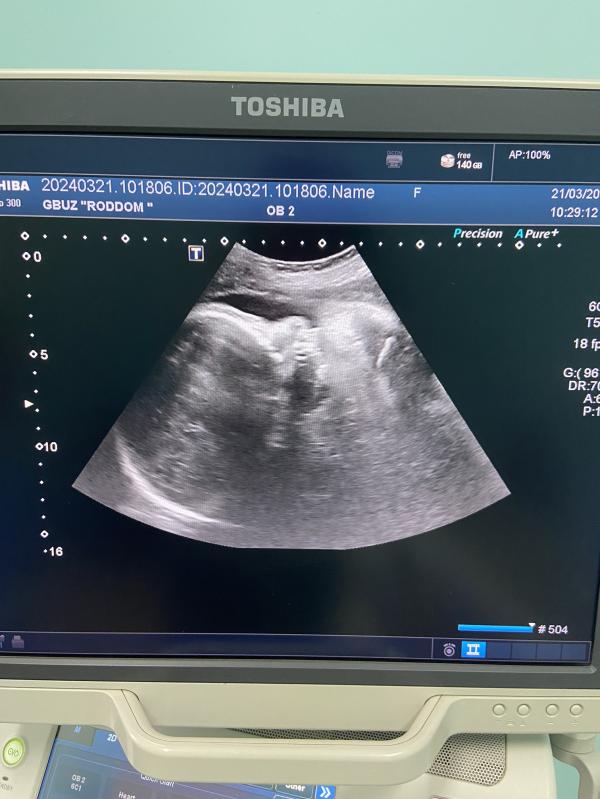

Узи 36.5 , вес 3012 гр ❤️

Было выявлено двойное обвитие на 3 скрининге в 30 нед, сейчас однократное.